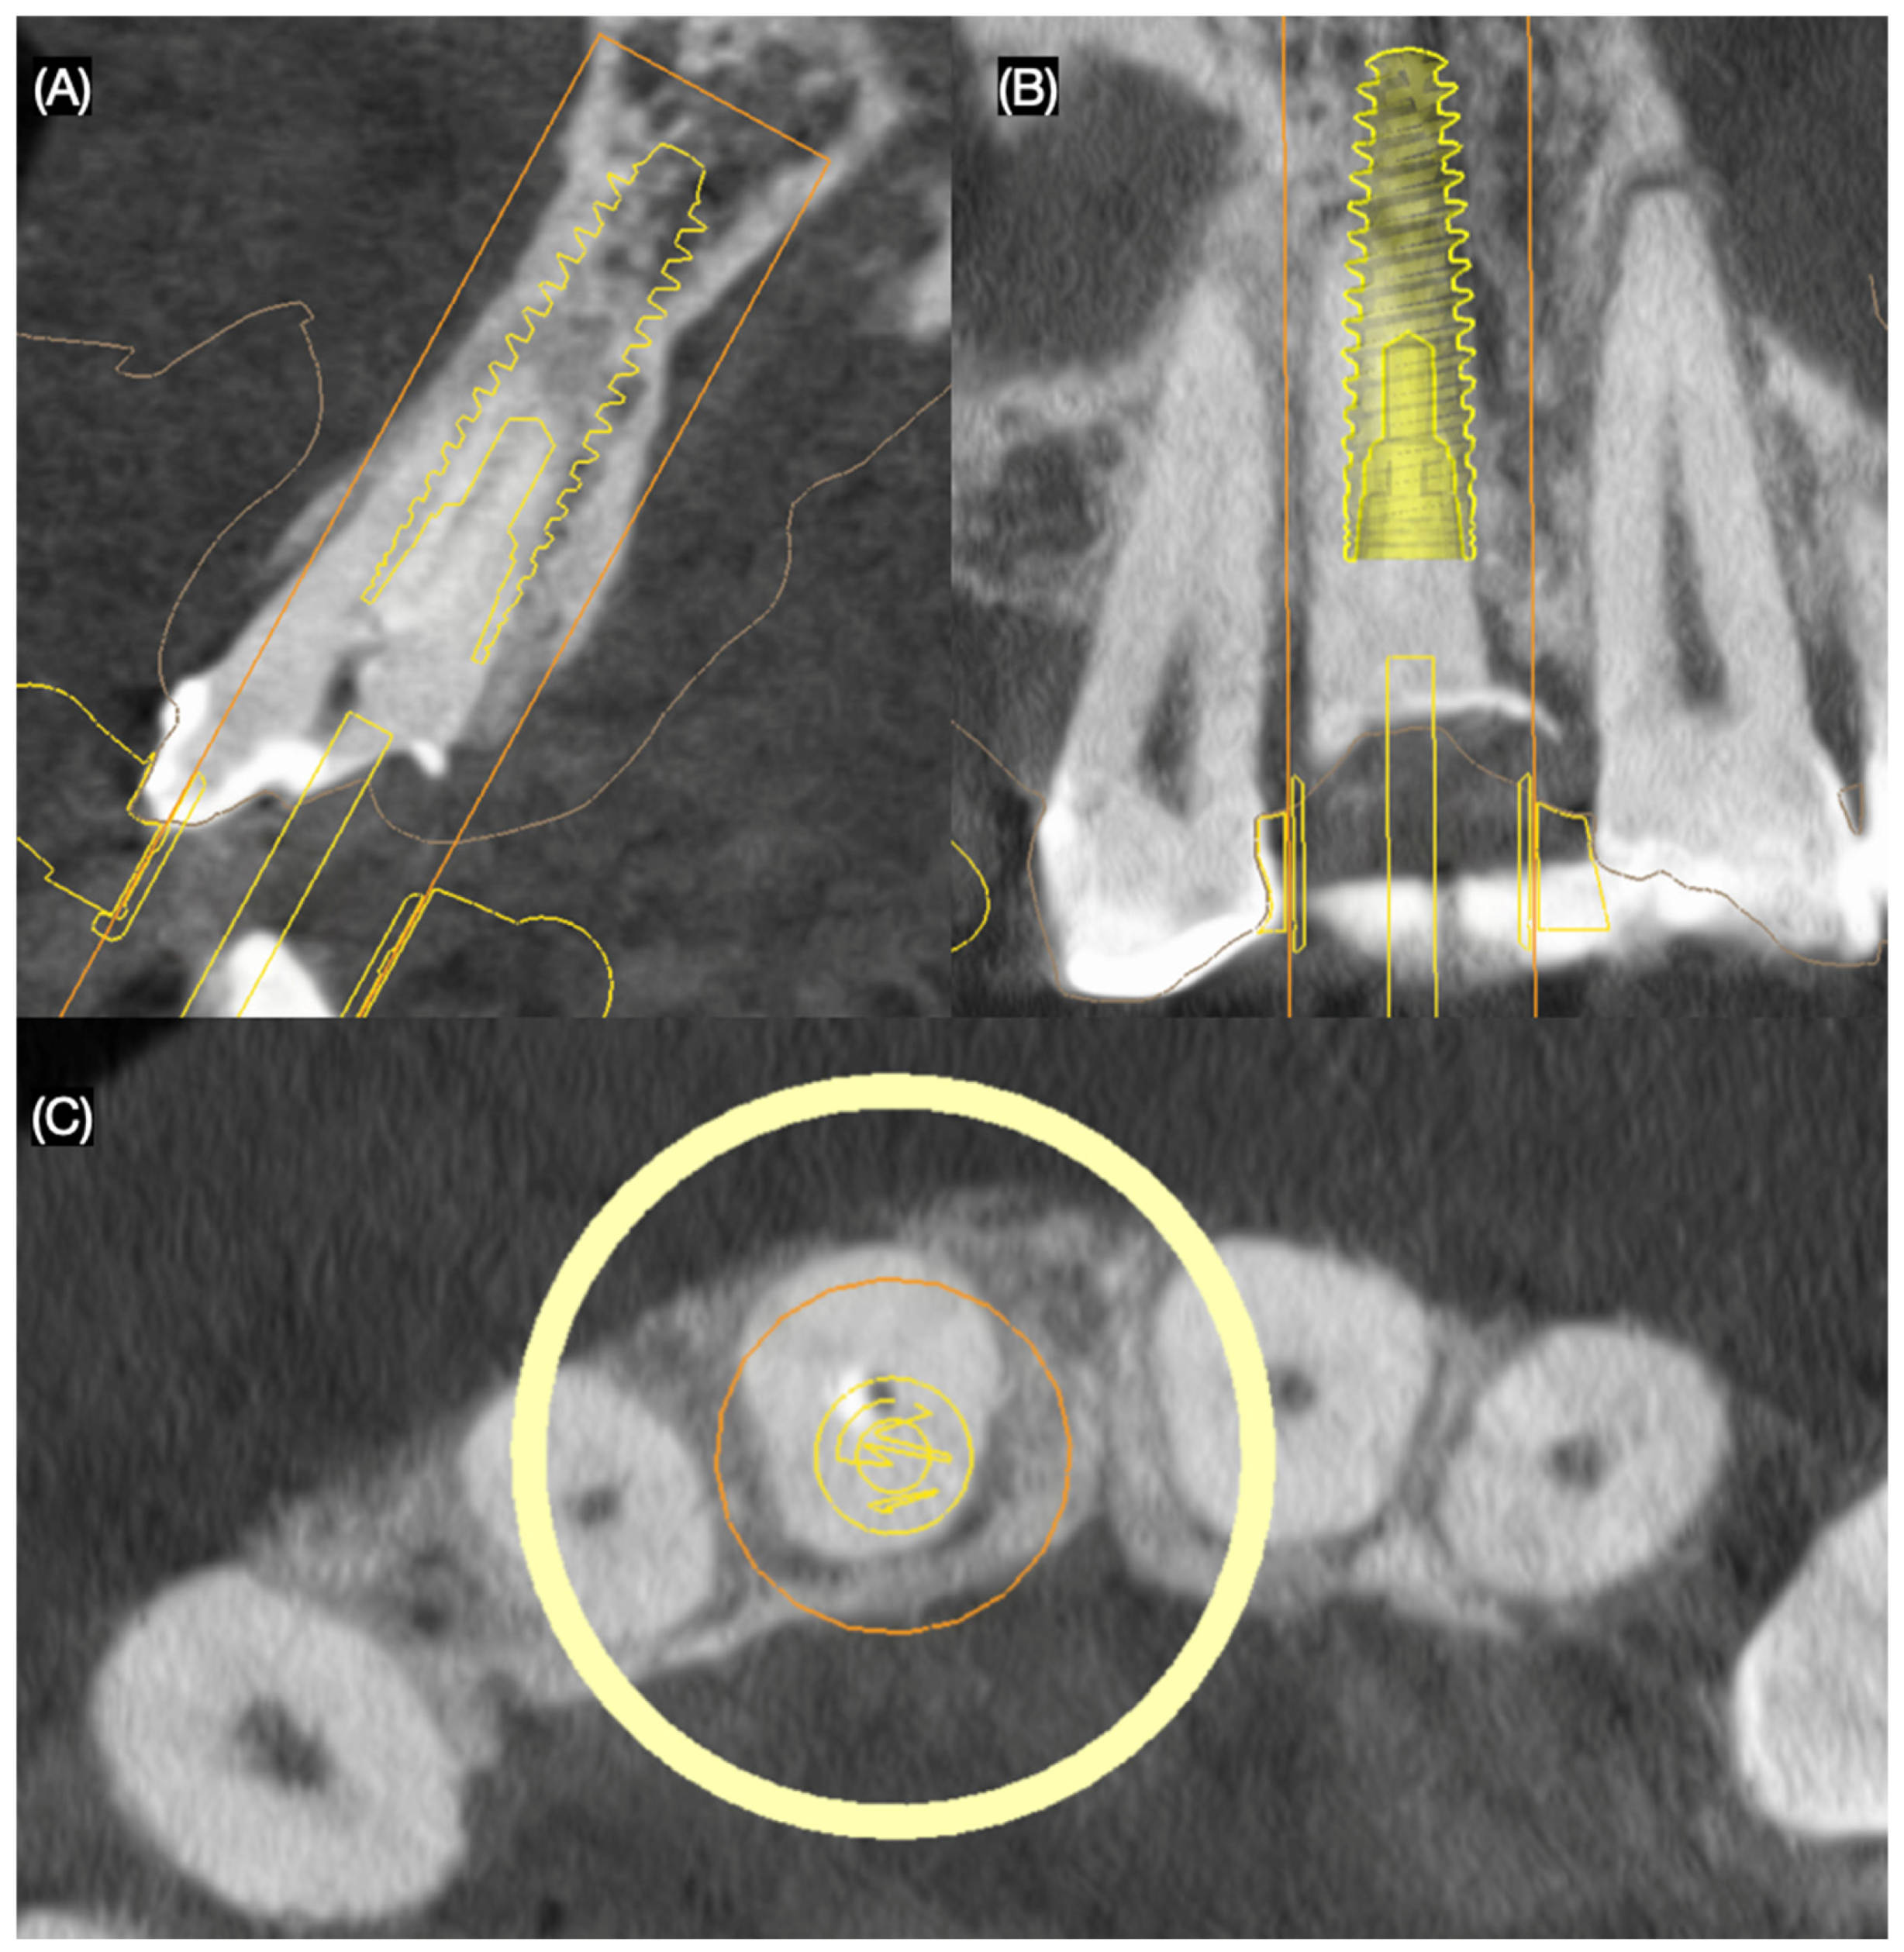

Based on clinical and radiographic findings, the patient was diagnosed with the following: A non-restorable, fractured maxillary right central incisor; old and stained resin composite restorations on both maxillary lateral incisors; and incisal wear on the maxillary canines, lateral incisors, and left central incisor. The patient was informed that due to the extent and location of the fracture, the maxillary right central incisor could not be salvaged and required extraction. A comprehensive treatment plan was proposed to address the patient’s functional and esthetic concerns, including the replacement of the non-restorable tooth and the enhancement of the anterior dentition. The plan consisted of the placement of a single immediate implant to replace the fractured maxillary right central incisor and ceramic veneers for the maxillary right lateral incisor, left lateral incisor, right canine, and left canine. A three-dimensional cone-beam computed tomography implant evaluation was also conducted (MSOFT, MIS Implant, Misgav, Israel) to assess the structural condition of the affected tooth and surrounding tissues. The evaluation revealed a subgingival horizontal fracture of the maxillary right central incisor (Figure 2).

Figure 2.

Three-dimensional implant evaluation with CBCT: (A) axial, (B) frontal, and (C) incisal view.